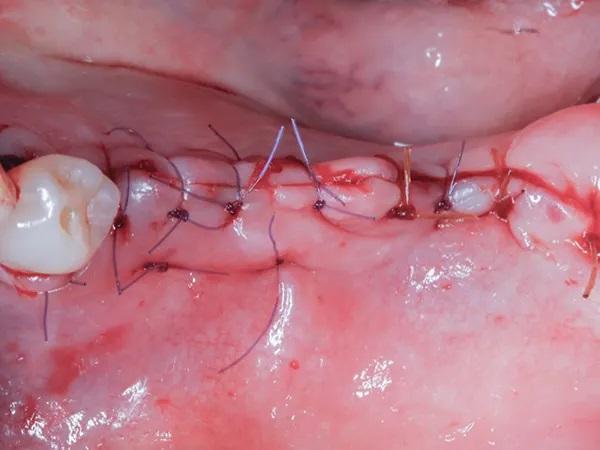

После этого шов затянули. Следили за тем, чтобы проколы язычного лоскута располагались не менее чем в 7 мм от края лоскута, чтобы в итоге можно было провести двухслойное ушивание горизонтальным матрасным и одиночным прерывистым швами. Ту же процедуру повторили по всей длине дефекта, чтобы обеспечить достаточную стабилизацию мембраны над композитным костным трансплантатом. После завершения стабилизации выполнили двухслойное первичное ушивание (Фото 7). Этого удалось добиться, наложив два горизонтальных матрасных шва на расстоянии 7-10 мм друг от друга, чтобы уменьшить натяжение по краям лоскута и оттянуть его. Наконец, одинарные простые прерывистые швы равномерно распределили в 5 мм от края лоскута по всей длине лоскута.

Фото 7: Первичное ушивание двумя горизонтальными матрасными швами для уменьшения натяжения по краю лоскута и одним простым прерывистым швом по всей длине лоскута.